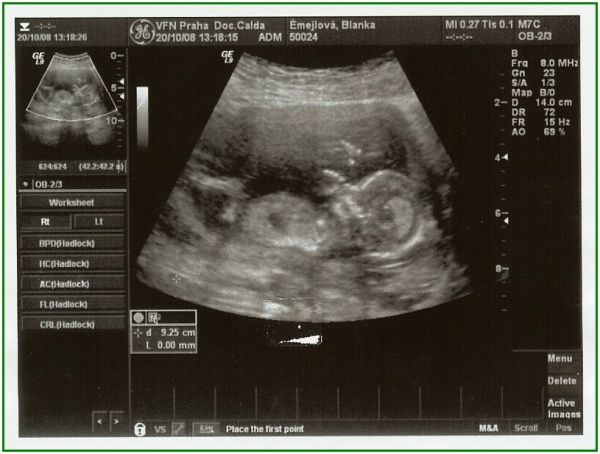

Pod pokličkou potřetí

Pěkně v teple pod kabátkem (25. týden)